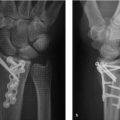

During a volar approach, it is essential that the extrinsic ligaments be repaired. Often, a zigzagor s-shaped capsulotomy will facilitate a tension-free closure (► Fig. 41.1).

During a dorsal approach, after measurement and prior to reaming, the K-wire may be driven into the trapezium to maintain reduction and prevent incidental pullout of the guide wire during reaming (► Fig. 41.2).